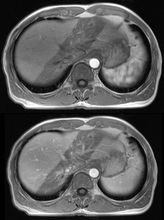

放射損傷的症狀

射線照射可引起兩類損傷:急性損傷(即刻效應)和慢性損傷(延遲反應)。急性輻射綜合徵能損傷很多器官。